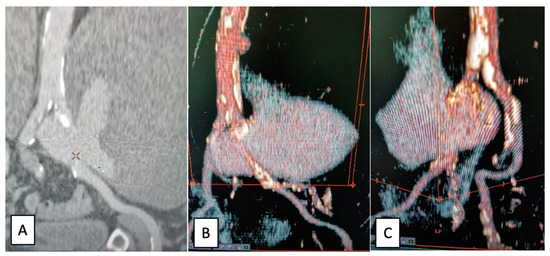

2.2. Case Report II